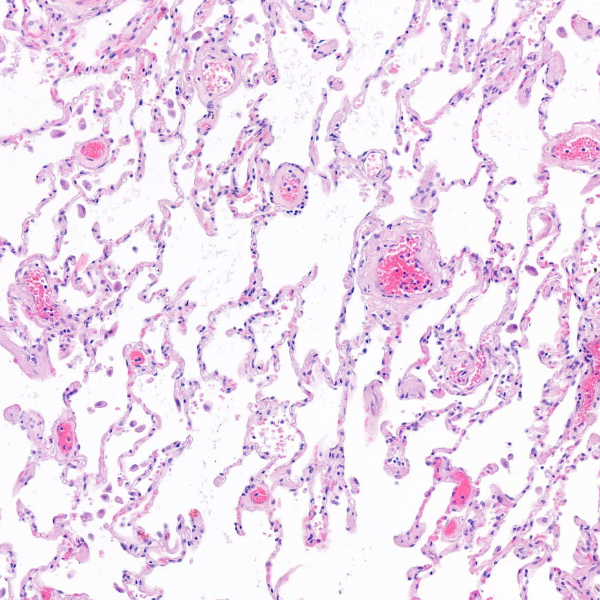

Gesundes Lungengewebe: Mikroskopische Aufnahme einer gesunden Lunge. Die weissen Bereiche sind Lufträume, dazwischen liegen feine Gewebestrukturen, in denen der Gasaustausch stattfindet.